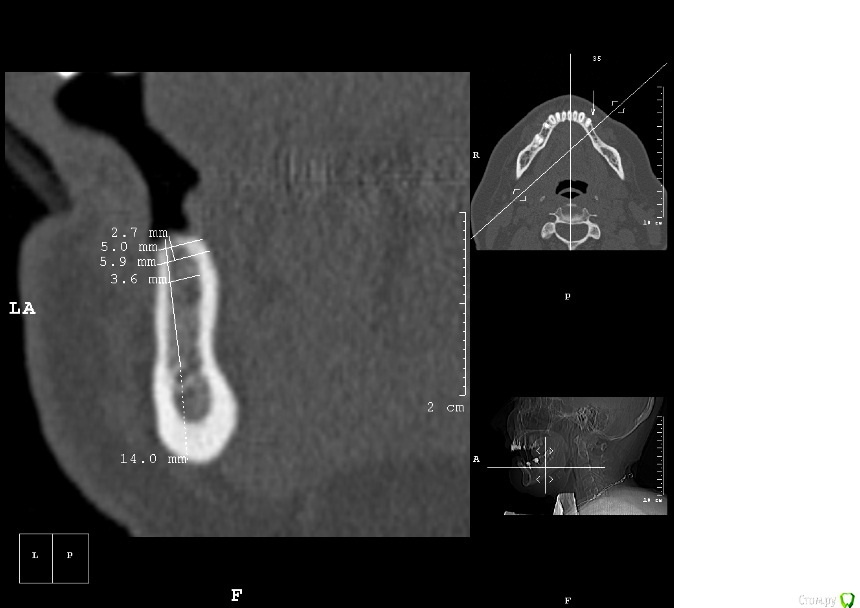

dantist_movani Опубликовано 2 мая, 2016 Поделиться Опубликовано 2 мая, 2016 Без обид, но срезы вообще ни о чем! Если есть рентгенолог или более опытный врач, сделайте новые срезы и залейте, посмотрим. Что хотите удалять, тоже не понял Ссылка на комментарий

dantist_movani Опубликовано 2 мая, 2016 Поделиться Опубликовано 2 мая, 2016 Спасибо, ответы давно уже получил, и дело не в срезах вовсе, чем вам срезы не угодили?на срезах указаны позиции 3.5,3.6,3.7,3.8? В какие позиции "3 винта" и что удалить, я просто может не понял? Ссылка на комментарий

kamranchick Опубликовано 2 мая, 2016 Автор Поделиться Опубликовано 2 мая, 2016 ну я указал 3 сегмент, 3 винта, следовательно удаление 5 го зуба, установка имплантатов в область 35 36 и 37 Ссылка на комментарий